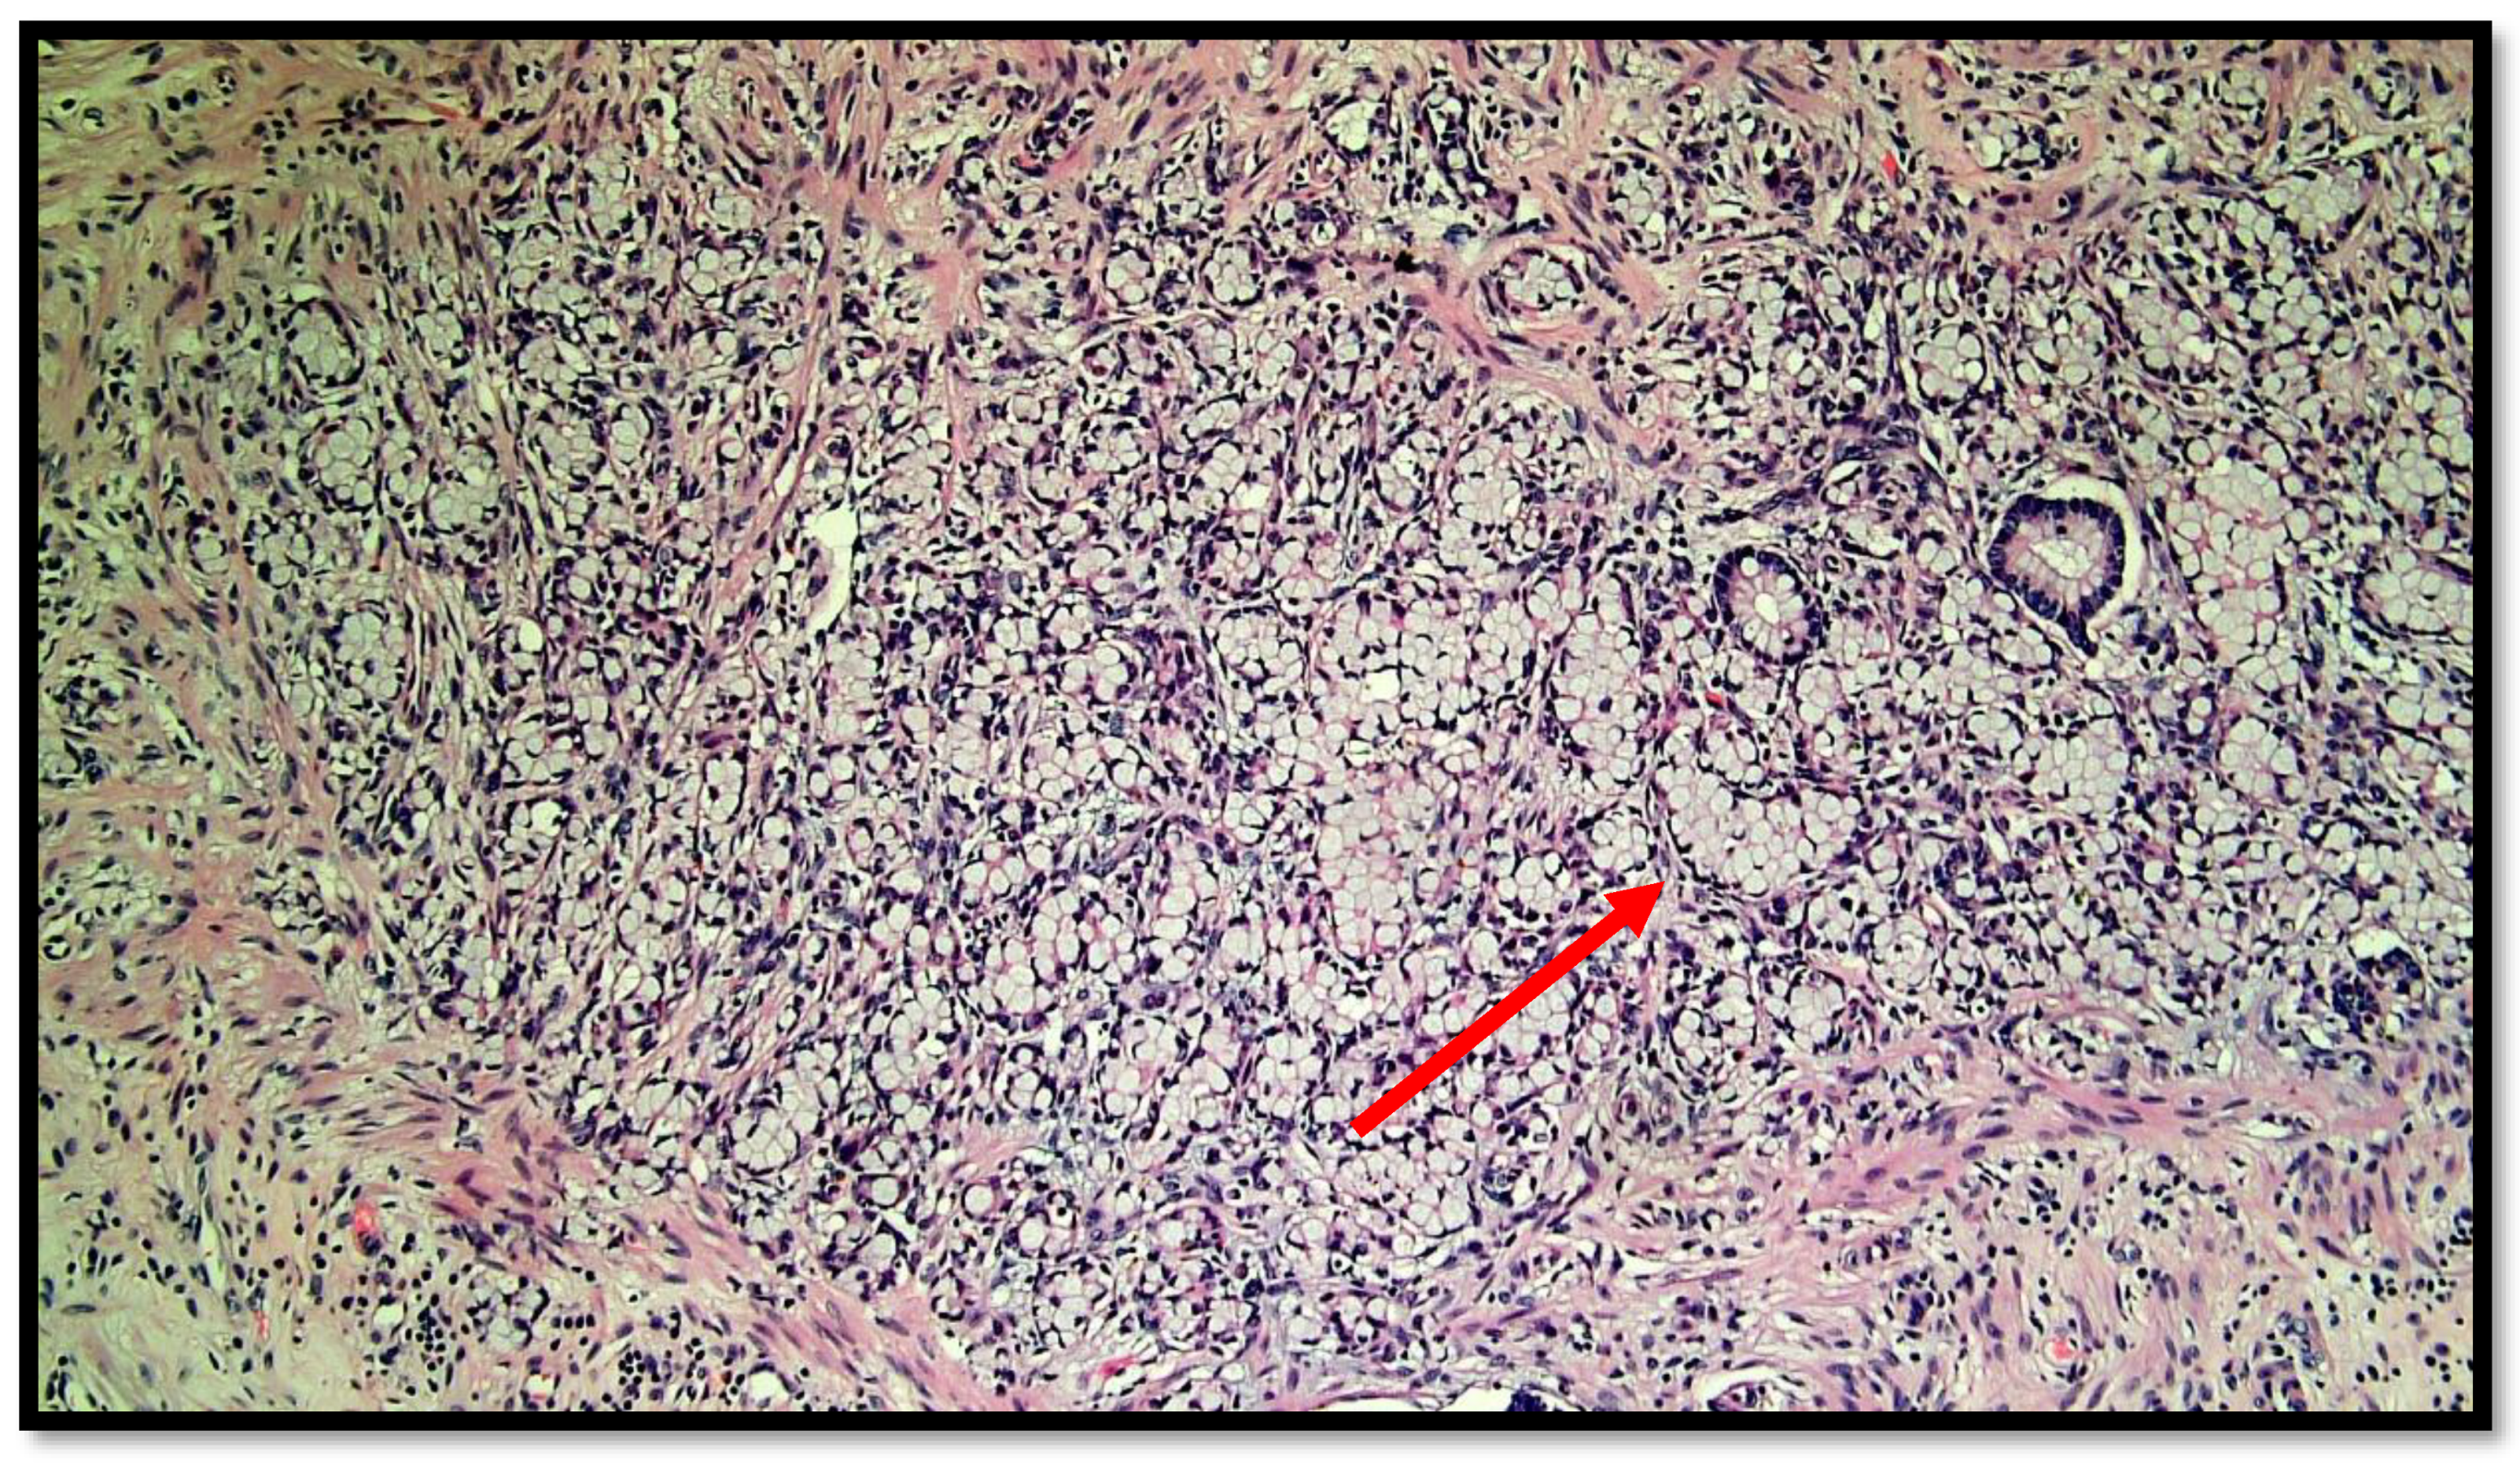

Figure 2.

Photomicrograph showing goblet cell carcinoid of the appendix. Cytological detail of the “ring with bezel” cells (hematoxylin–eosin, original magnification: 20×). An example of a ring with bezel cells is indicated with a red arrow.